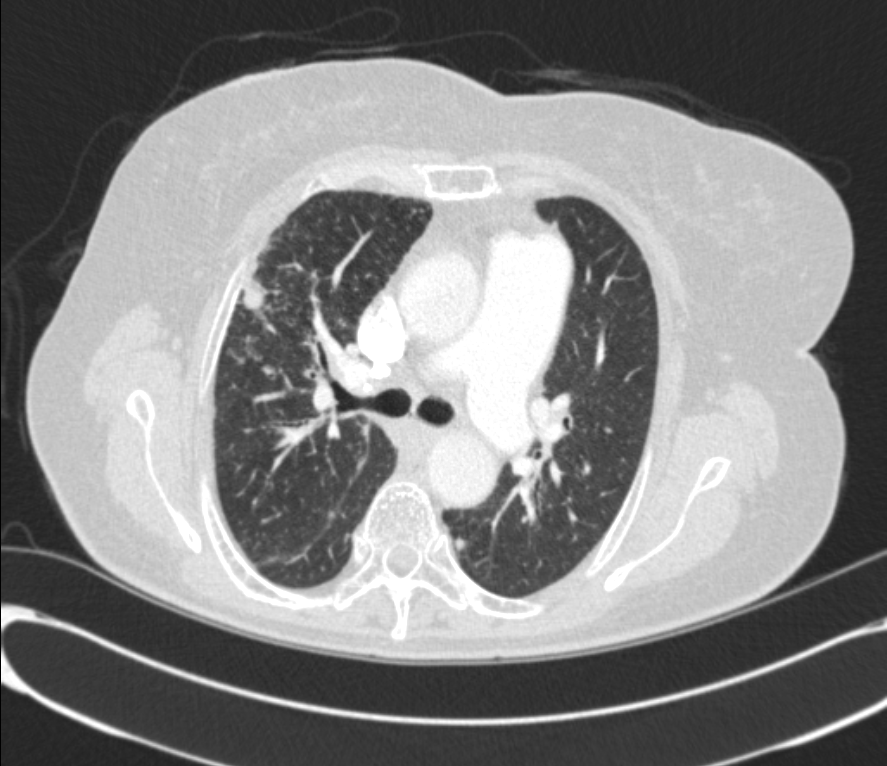

DOE  ÁּҷΠ evaluation  À§ÇØ ÃÔ¿µÇÑ  CXR ¹× chest CT ¼Ò°ßÀÔ´Ï´Ù.

* CXR °ú  chest CT  »çÁøÀÔ´Ï´Ù.

¶Ñ·ÇÇÑ ¿µ»óÀ» À§ÇØ f/u Áß¿¡ ÂïÀº »çÁøÀ» ÷ºÎÇÏ¿´½À´Ï´Ù.

l  Chest CT

Progression of multiple small nodules in both lungs, along peri-BV and ILS, dominant on RUL and RML. No significant change of several small LNs in both hilar and mediastinum.   COPD: diffuse bronchitis. LH enlarge and PAH.